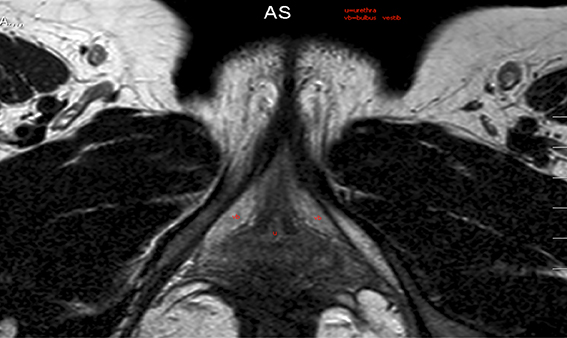

Figure 5: MRI of the clitoral crurae.

In 2010 the first patient came to our outpatient clinic with the request for genital reconstruction after FGM. Since that time there has been a steady stream of patients coming to our clinic. Many of these women have a common history of fleeing warzones in Africa and also being victims of war violence. Furthermore many of these women could still recall the trauma of the initial rite. By taking the decision to undergo genital reconstruction these women are facing the possibility of being alienated from their own family and culture. While treating these patients it is essential to keep this social / cultural context in focus. We try to match the patient with a female case manager whom the patient can approach for support and information and who can be an advisor throughout the course of treatment. In the beginning we take scans to visualise the clitoral stump (Figure 5). At present we are operating on at least two patients a month. The operation can be done as a day surgery procedure under general anaesthesia. If the patient also wants a labia minora reconstruction then they need to be admitted for at least 24 hours. See Figure 6 for surgical photographs of the reconstruction.